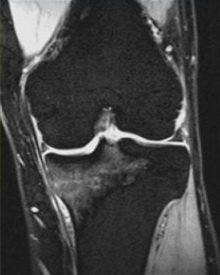

Рентген в данном случае почти неинформативный, поэтому врач должен провести дополнительные методы обследования. Преимущественно для подтверждения наличия стрессового перелома назначают МРТ диагностику. Он является наиболее чувствительным методом для выявления стрессового перелома, а также может быть полезен для дифференциации при повреждении связок/ хряща от повреждения костей.

Типичные признаки стрессового перелома на МРТ включают:

- отек надкостницы или прилегающих мягких тканей;

- отек костного мозга;

- линия гипоинтенсивного перелома T1 определяется при тяжелой травме.